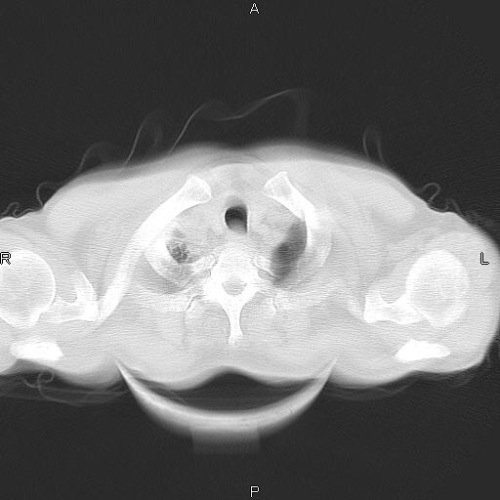

CT病例讨论

CT49619:肺部

查体见右肺上叶异常

右肺上叶淡磨玻璃影,考虑炎症改变。

特发性肺间质纤维化 ?

右上间质肺改变